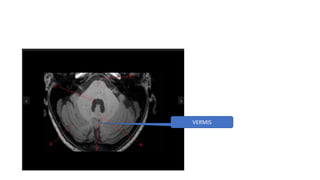

CEREBELLUM

TONSIL

CEREBELLAR

HEMISPHERE

VERMIS

MIDDLE CEREBELLAR PEDUNCLE

SUPERI0R CEREBELLAR PEDUNCLE -MIDBRAIN LEVEL

HORRIZONTAL FISSURE

SUPERIOR CEREBELLAR PEDUNCLE -MIDBRAIN LEVEL

MIDDLE CEREBELLAR PEDUNCLE AT PONS